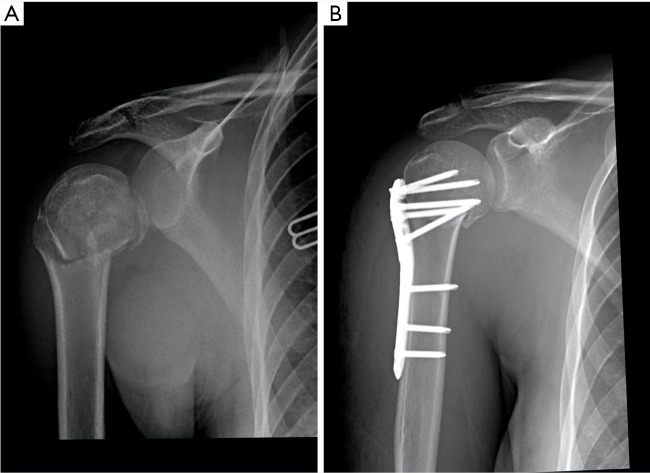

Key content and findings: Patients with minimally displaced fractures should be treated nonoperatively. Internal fixation with intramedullary nailing is a viable option in cases of two-part surgical neck fractures, those with diaphyseal involvement and no significant displacement of the tuberosities, or pathologic fractures. Those elderly patients with displaced three- or four-part PHFs fractures with intact rotator cuff muscles should be treated with locking plate fixation if anatomical reduction of fracture fragments including tuberosity is possible, as the results after union despite avascular necrosis are favorable. Moreover, patients with failed fixation treated with salvage reverse shoulder arthroplasty (RSA) have similar outcomes to RSA for acute PHFs. Hemiarthroplasty should be reserved for select group of young active patients with unconstructable fracture, intact rotator cuff, and good tuberosity bone stock. RSA should be offered as first option for elderly patients with poor bone stock, rotator cuff insufficiency, fracture dislocations, head-split fractures, and severely displaced 3- and 4-part PHFs.

Abstract Image